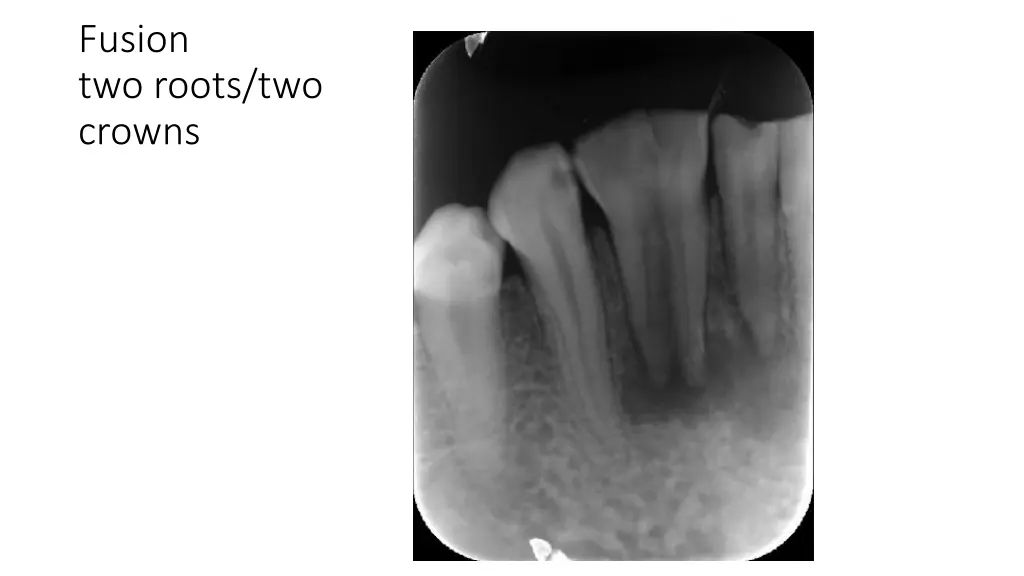

Fusion two roots/two crowns